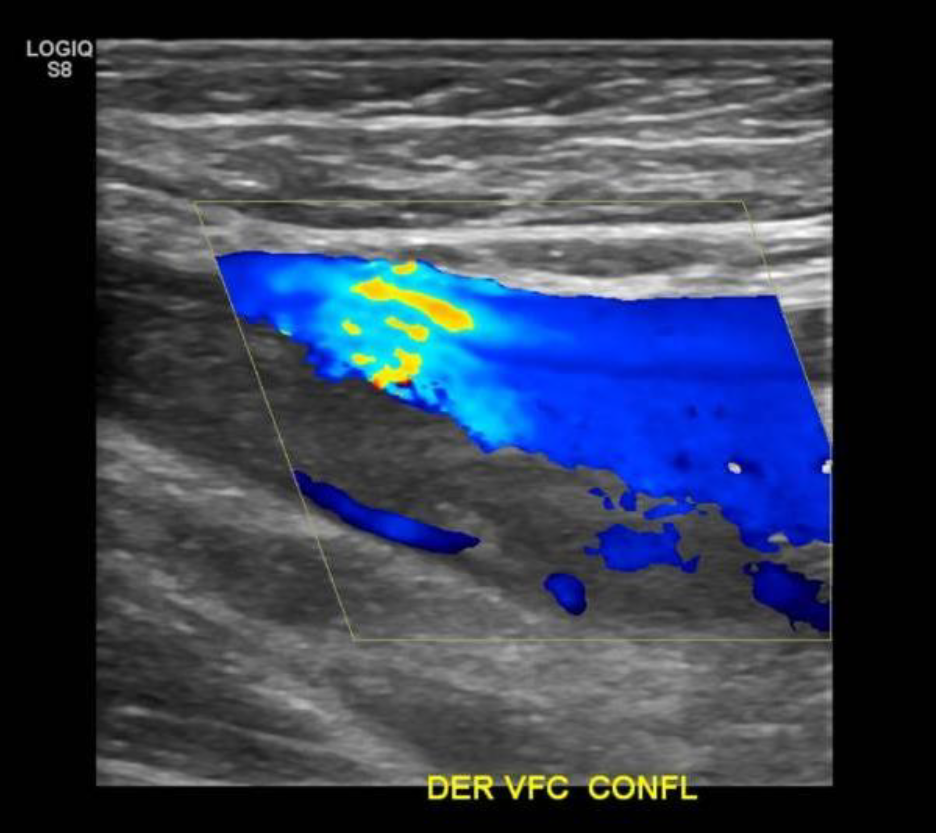

• Desde la VFC se visualiza contenido ecogénico interno, no compresible y sin señal al Doppler Color sugerente de Trombo que se extiende por toda la cara posterior del muslo comprometiendo a la Vena Femoral Profunda. Vena Femoral Superficial permeable.

Hallazgos: Piel y tejido subcutáneo sin alteraciones. Material ecogénico endoluminal en vena femoral común, vena femoral superficial y profunda, con ausencia de flujo y compresibilidad, compatible con trombosis venosa profunda en evolución. Planos musculares de aspecto ecográfico conservado, sin evidencias de desgarros fibrilares. Engrosamiento disminución de ecogenicidad inserción proximal de los isquiotibiales, sin desgarros. No se observan lesiones nodulares ni quísticas. Contornos óseos visualizables regulares. Impresión

Diagnóstico: Hallazgos compatibles con trombosis venosa profunda de vena femoral común, vena femoral superficial y profunda. Es indispensable evaluación clínica de urgencia. Entesitis proximal de los isquiotibiales.